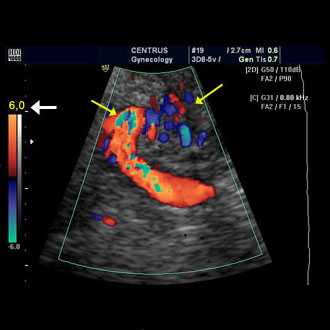

Doppler ultrasound is a special ultrasound technique that evaluates blood as it flows through a blood vessel, including the body's major arteries and veins in the abdomen, arms, legs and neck.

In an ultrasound examination, a transducer both sends the sound waves into the body and receives the echoing waves. ... Doppler ultrasound, a special application of ultrasound, measures the direction and speed of blood cells as they move through vessels.

“Fetal Dopplers are safe when used and interpreted by a health care provider, such as a nurse, midwife or physician,” Chanchani says. “They provide real-time information about whether the heart rate of a baby is normal. The risk of using fetal Dopplers at home is not in the technology.